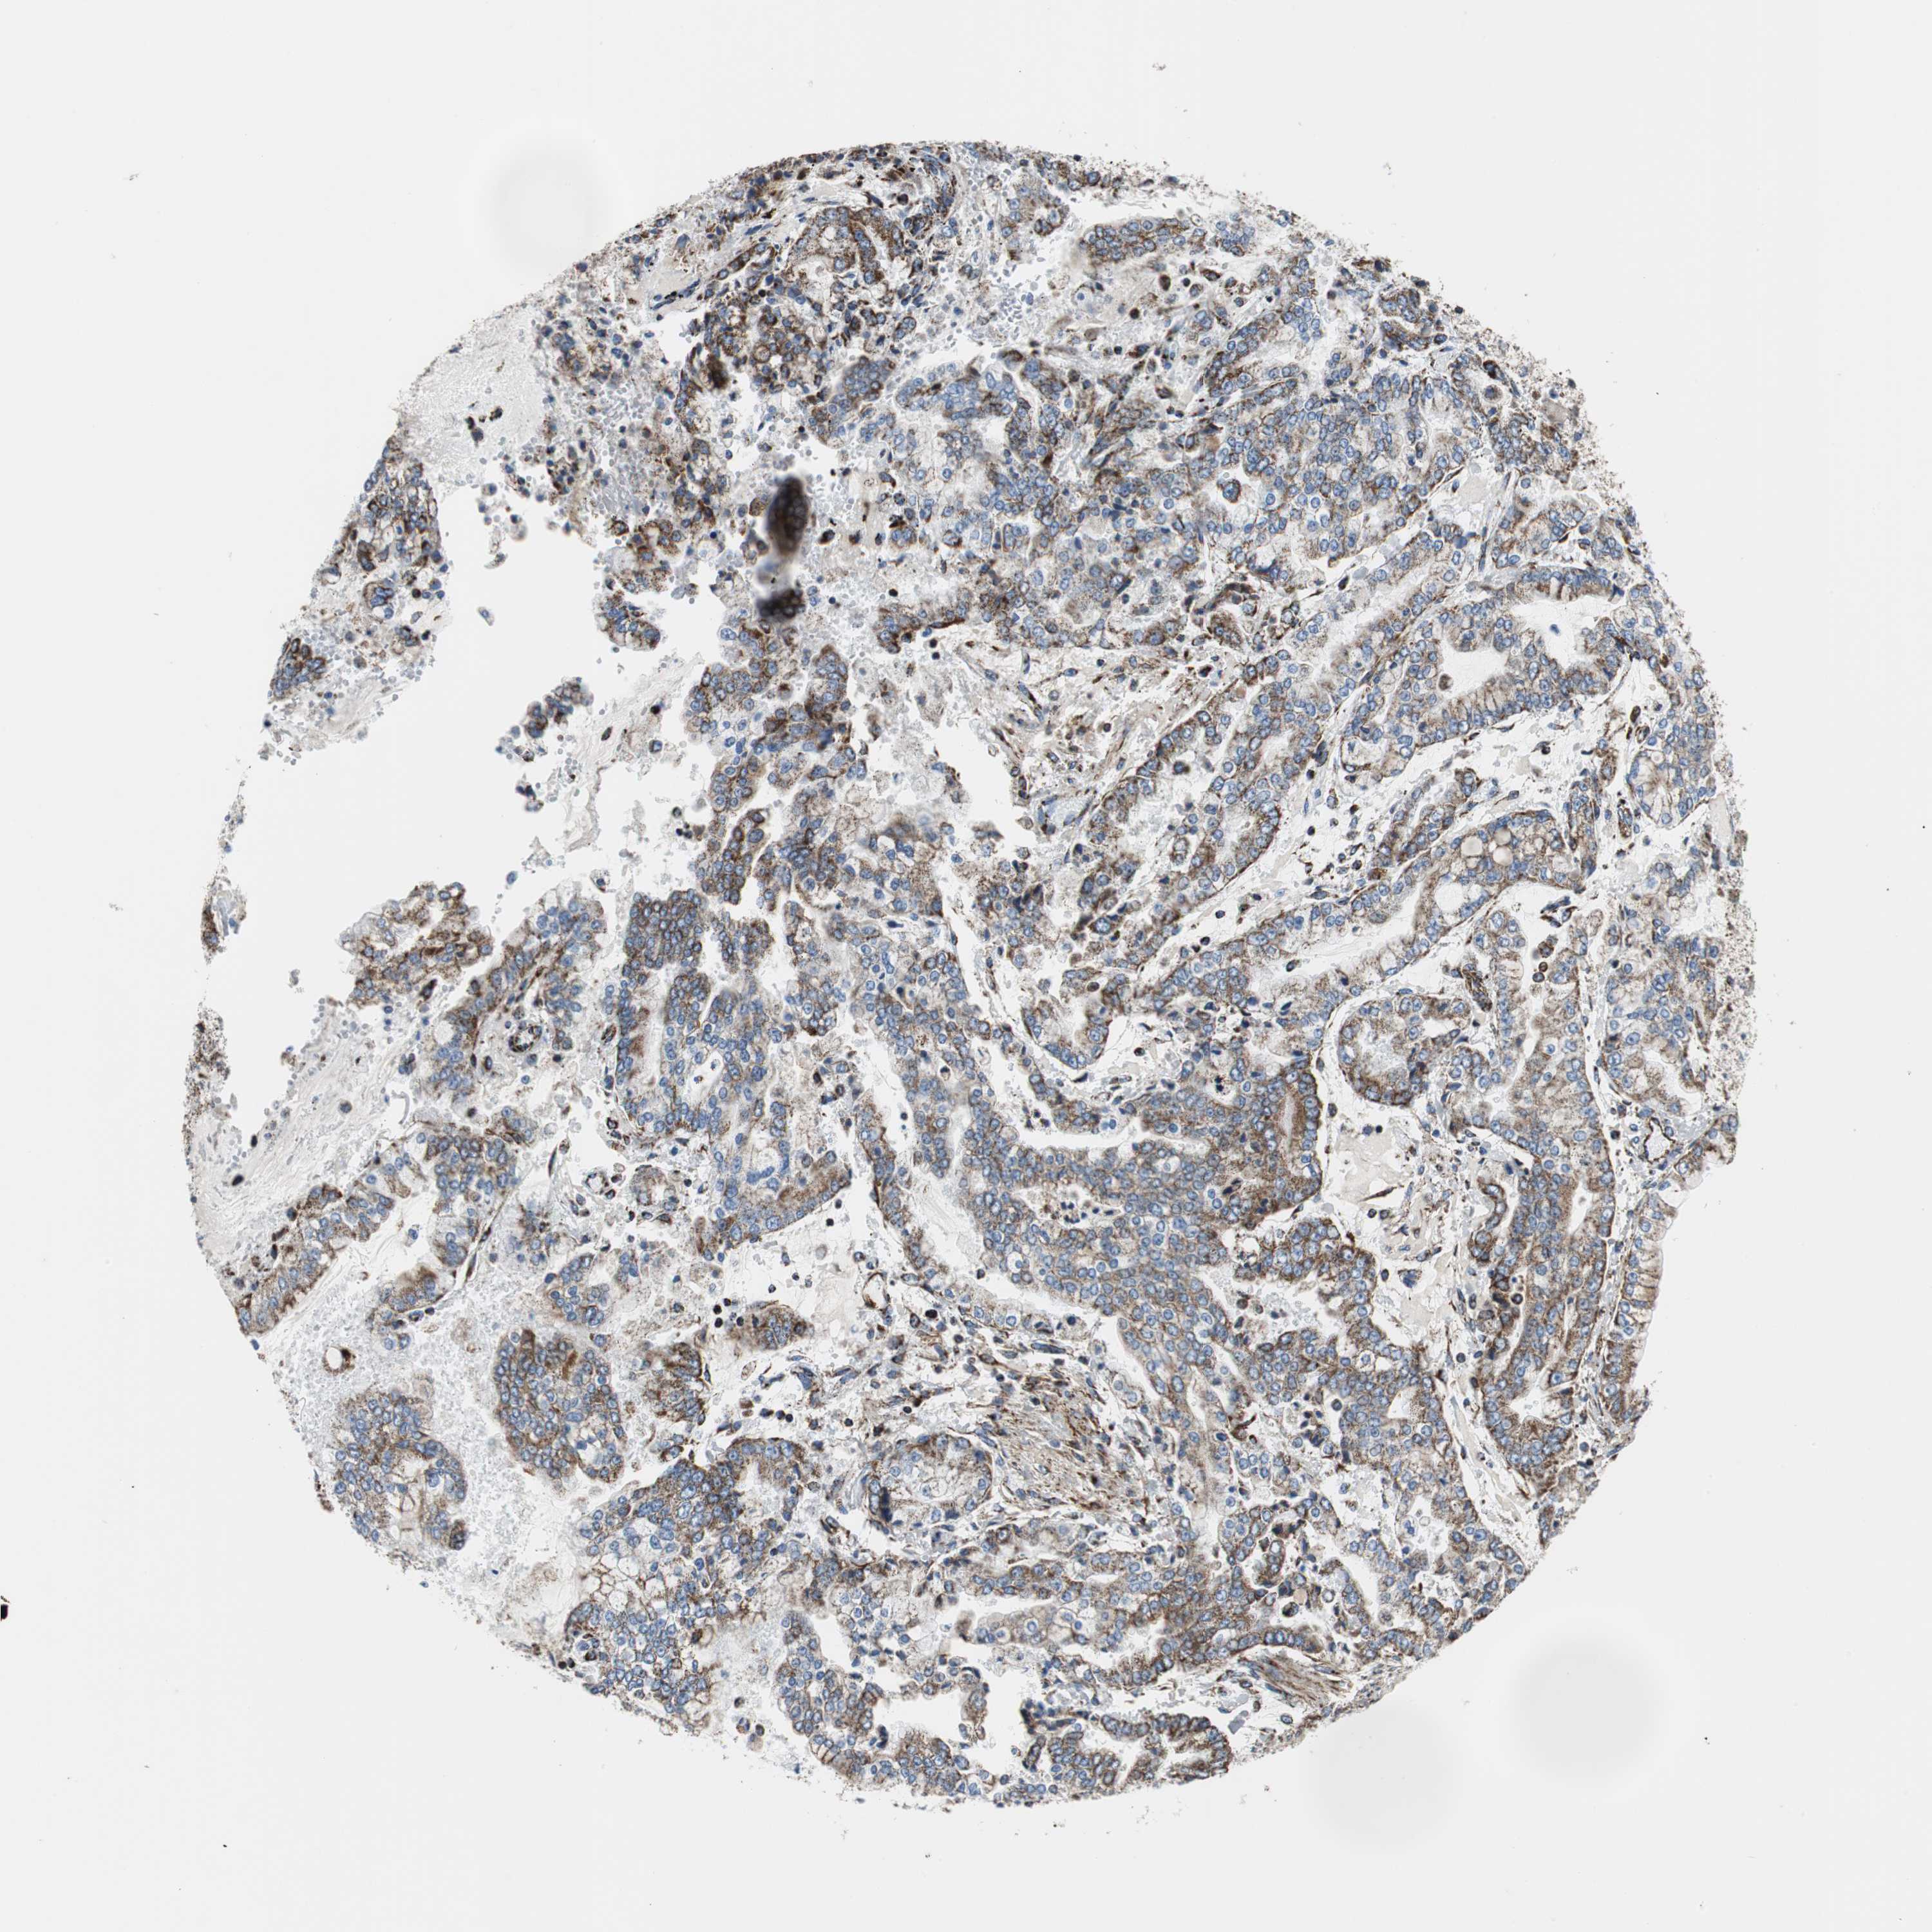

STOMACH CANCER - Protein expressioni

A mouse-over function shows sample information and annotation data. Click on an image to view it in a full screen mode. Samples can be filtered based on level of antibody staining by selecting one or several of the following categories: high, medium, low and not detected. The assay and annotation is described here.

Note that samples used for immunohistochemistry by the Human Protein Atlas do not correspond to samples in the TCGA dataset.

Antibody stainingi

Antibody staining in the annotated cell types in the current human tissue is reported as not detected, low, medium, or high, based on conventional immunohistochemistry profiling in selected tissues. This score is based on the combination of the staining intensity and fraction of stained cells.

Each image is clickable and will lead to virtual microscopy that enables deeper exploration of all samples and also displays staining intensity scores, fraction scores and subcellular localization as well as patient and tissue information for each sample.

Antibody HPA051797

Antibody CAB007055

Staining

High

Medium

Low

Not detected

Intensity

Strong

Moderate

Weak

Negative

Quantity

>75%

75%-25%

<25%

None

Location

Nuclear

Cytoplasmic/membranous

Cytoplasmic/membranous,nuclear

Adenocarcinoma, NOS

Adenocarcinoma, High grade